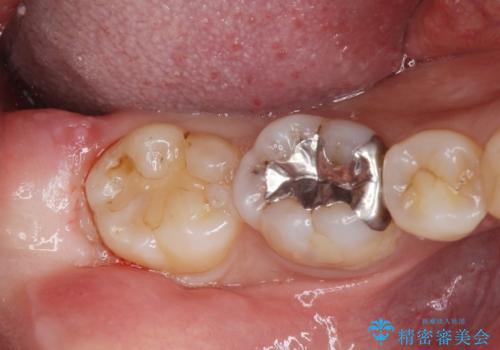

歯ぐきの形を整え、外れにくい被せ物を装着

歯の高さを出すための親知らず抜歯と歯肉切除